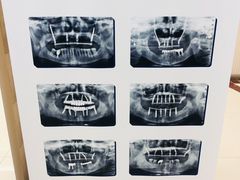

• 泰康拜博口腔(凯迪大厦店)

• -泰康拜博口腔(凯迪大厦店)

匿名用户 | 21-06-19